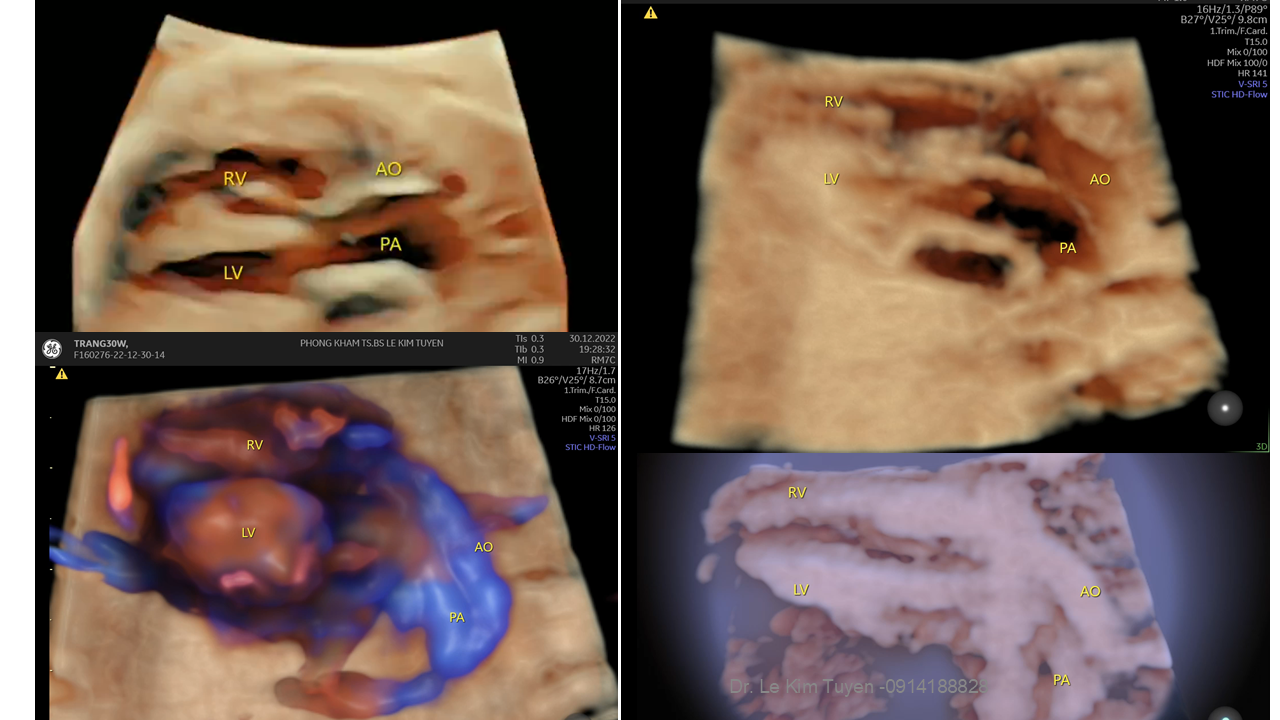

Áp dụng công nghệ Graphicflow trong phát hiện bệnh tim bẩm sinh cần cấp cứu sơ sinh

TS. BS. Lê Kim Tuyến

Bệnh viện Tim Tâm Đức